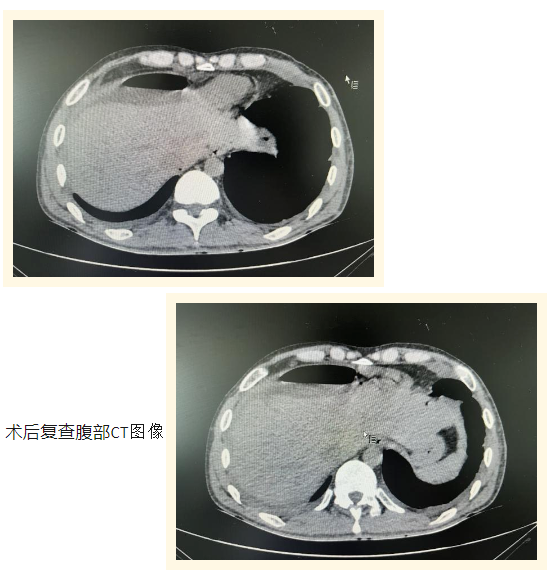

术前腹部CT中显示的肝内异物

近日,兴安盟人民医院肝胆外科团队圆满完成了一项高难度的“腹腔镜下肝脏异物取出术”,成功从一名中年男性患者的肝脏内精准取出四枚钢针,标志着我院在此类复杂手术领域取得了新的突破。该患者因体内异物导致胸腹部剧烈疼痛并伴有呼吸困难,紧急到我院急诊科就诊。经详细询问病史得知,患者在19天前先后五次将针状异物刺入双侧胸壁,随后出现双侧胸部持续性疼痛。不幸的是,症状于一天前急剧恶化,呼吸困难加剧,胸部疼痛难忍,遂到我院寻求进一步治疗。肝胆外科主任医师邢国权迅速响应,第一时间赶赴现场。通过细致的病史询问、体格检查及影像学资料分析,明确诊断患者肝脏内存有四处金属异物影像,并立即建议实施手术治疗。鉴于异物可能因患者肢体活动或体位变化而发生移位,进而刺破关键血管,严重威胁患者生命安全,医院迅速启动了多学科协作机制。在肝胆外科贾智硕主任的主持下,组织了多学科专家会诊,经过充分讨论,决定采用先进的腹腔镜技术实施肝内异物取出术。手术由吉林大学中日联谊医院对口支援我院肝胆外科的刘宏宇主任医师主刀,邢国权主任医师及张志强医师作为助手,手术在全身麻醉下进行。